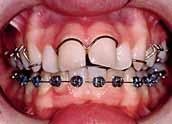

3. Anterior bite plan to reduce the overbite and bonding the lower arch (Figure 5).

The treatment of the case was planned in stages. Stage one consistedof improving the oral hygiene of the patient and management of all carious lesions and assesses the compliance and attitude of the patient towards orthodontic treatment. The next stage involved the reduction of the overbite. The patient presented with a deep overbite that was causing damage to the palatal mucosa (Figure 2). This was achieved with an anterior bite plane removable appliance and bonding of the lower arch. This appliance will free the occlusion of the buccal segment teeth and if worn consistently, will “passively” limit further eruption of the incisors but allow the lower premolars to erupt, thus reduce the increased overbite (Figure 5).